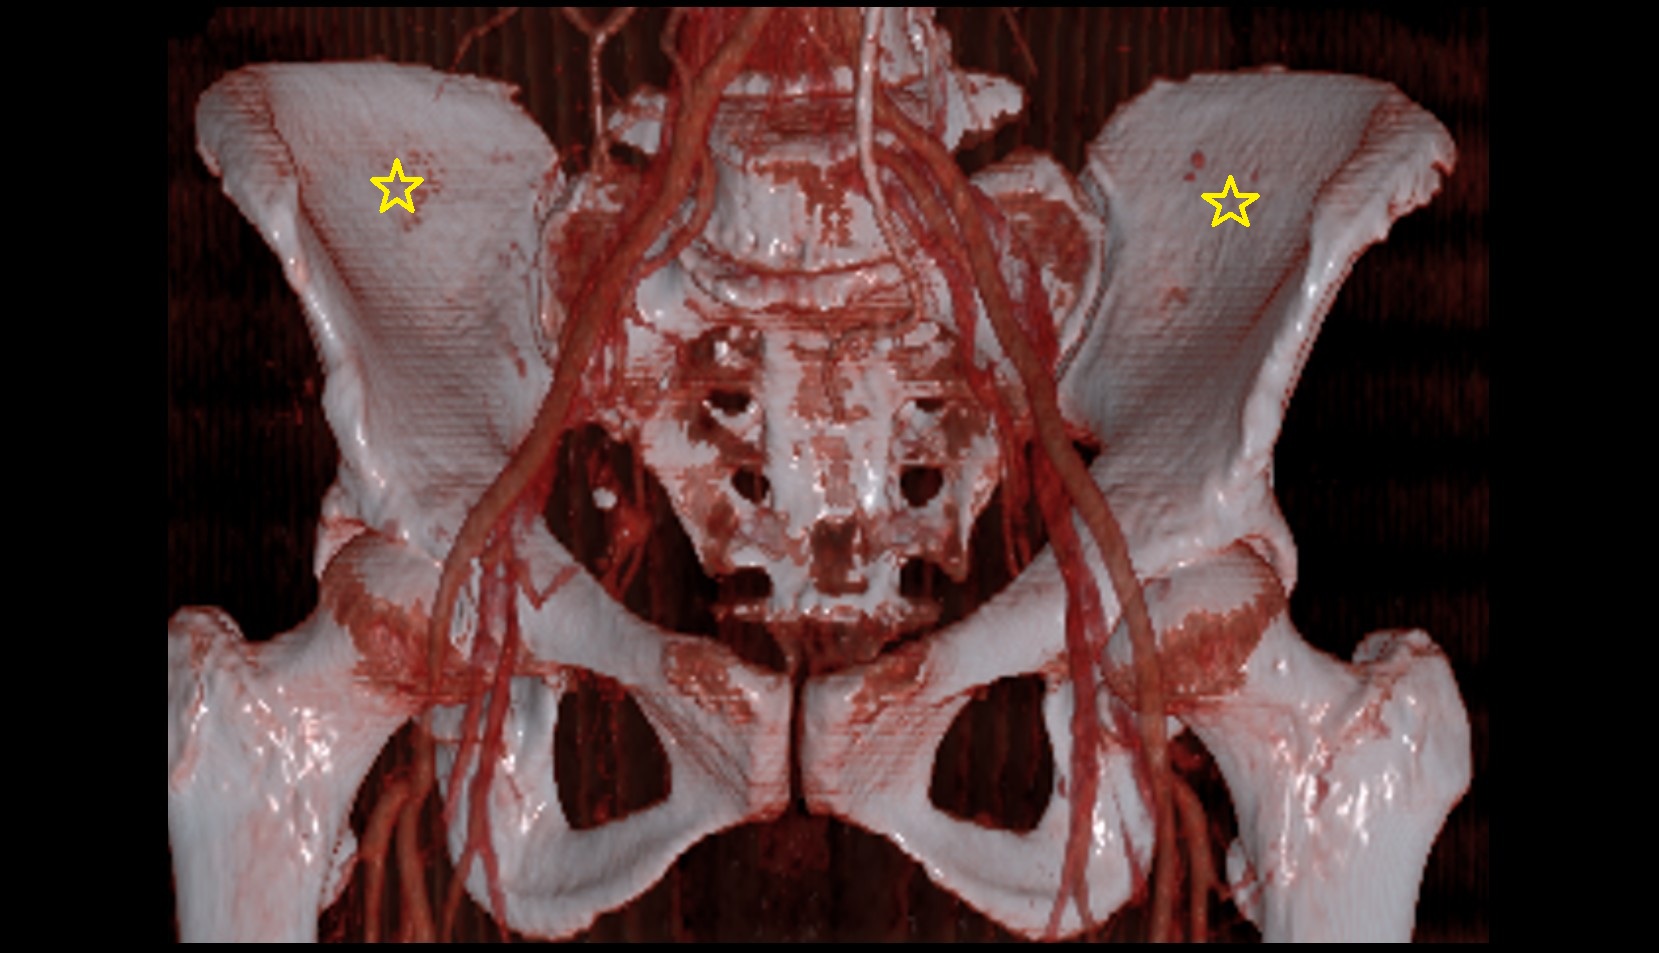

- Aortic bifurcation

- External iliac artery

- Internal iliac artery

- common iliac artery